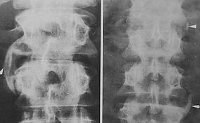

Проводится рентгенологическое исследование суставов, артроскопия, диагностическая пункция сустава с последующим исследованием синовиальной жидкости. Рентгенография позвоночника может выявить двусторонний сакроилеит, обызвествление связок позвоночного столба, паравертебральные оссификации.